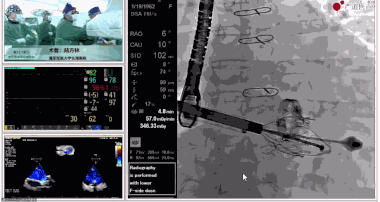

圖片

▲瓣膜植入前右心室造影